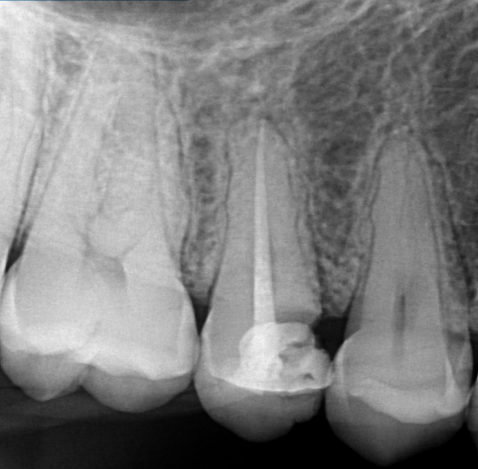

Paciente de 24 anos de idade procurou atendimento odontológico para o dente 15. Segundo o paciente, há 2 dias, ao se alimentar, acabou fraturando um pedaço do dente. Ao exame clínico, foi observada fratura da cúspide palatina subgengival, falta de material restaurador na mesial e presença de bom remanescente dental nas faces vestíbula e distal, sem necessidade de indicação para reabilitação com retentor intrarradicular e coroa protética com fenótipo periodontal espesso. Ao exame radiográfico, foi observado tratamento endodôntico realizado, ausência de lesão periapical e a lesão cariosa que originou a fratura, a qual estava localizada ao nível da crista óssea com os tecidos de inserção supracrestal violado (espaço biológico). Comprimento do dente na radiografia periapical – 21,0 mm, coroa anatômica com 7,0 mm da oclusal à junção cemento-esmalte. Observe a radiografia a seguir:

Com base na radiografia periapical e nas informações clínicas do caso, defina a viabilidade de se realizar tratamento cirúrgico para reestabelecer os tecidos de inserção supracrestal e qual o tratamento indicado.